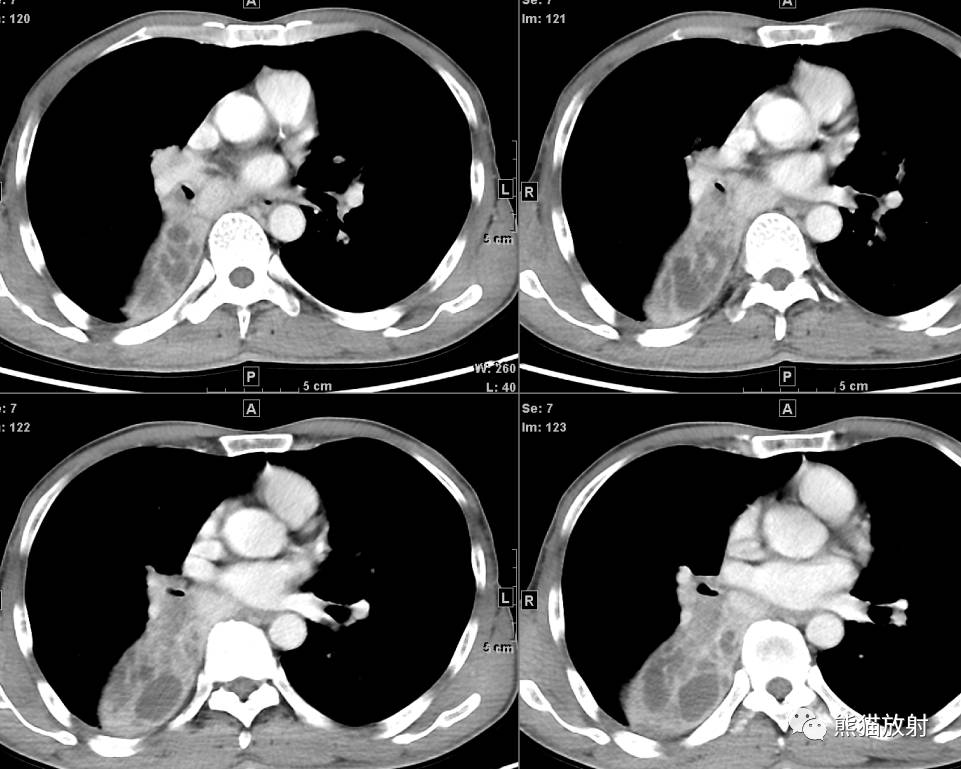

↓ 右肺中央型肺癌(鳞癌)并右下肺不张(X、CT)